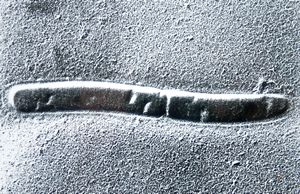

Borrelia Burgdorferi isolated from liquor